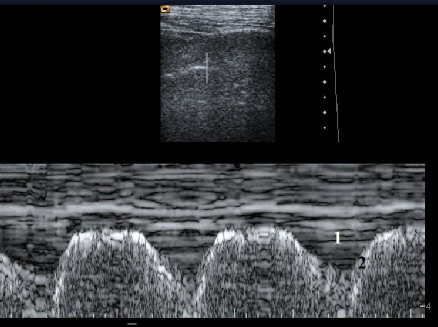

Enregistrement en mode TM (Time Mouvement) d’un épanchement pleural minime. Notez la cinétique respiratoire de l’épanchement.

1 : épanchement pleural

2 : surface pulmonaire

Cette cinétique respiratoire de l’épanchement pleural minime peut être enregistrée en mode TM et s’oppose bien entendue à l’immobilité de la pachypleurite